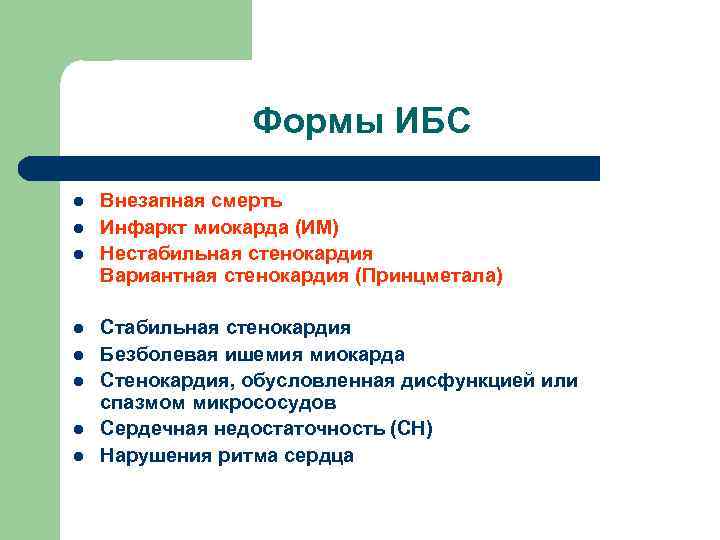

Формы ИБС l l l l Внезапная смерть Инфаркт миокарда (ИМ) Нестабильная стенокардия Вариантная стенокардия (Принцметала) Стабильная стенокардия Безболевая ишемия миокарда Стенокардия, обусловленная дисфункцией или спазмом микрососудов Сердечная недостаточность (СН) Нарушения ритма сердца